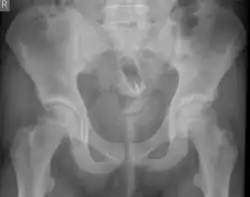

Стеклянная бутылка в просвете прямой кишки на рентгенограмме | |

Обычно делают несколько рентгеновских снимков, чтобы точно определить место нахождения инородного тела. Инородные тела из малоконтрастного материала (например, пластика) могут потребовать ультразвукового исследования или компьютерной томографии.[28] Магнитно-резонансная томография противопоказана, особенно если неизвестен материал инородного тела. Инородные тела прямой кишки могут проникать глубоко в толстую кишку, при определённых обстоятельствах вплоть до правого изгиба ободочной кишки.[9]